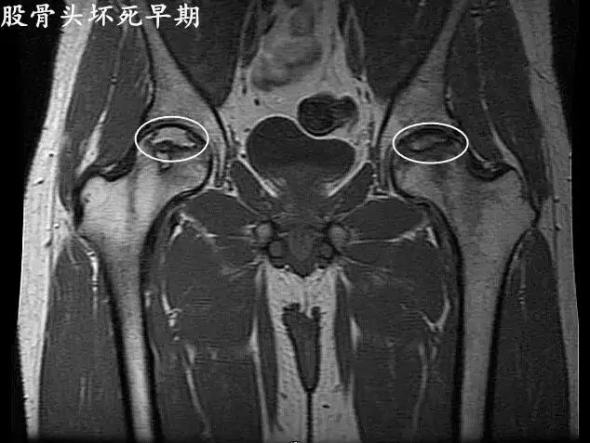

股骨頭壞死早期信號有哪些?北京公立三甲醫院骨傷科主任醫師王春。股骨頭壞死發病的早期信號有哪些?股骨頭壞死可以有很長的潛伏期,在發病以后早期的癥狀一般不明顯,非常容易被患者忽視。提示大家如果有以下癥狀就要提高警惕。

股骨頭壞死最初的癥狀就是疼痛,它可以出現在腹股溝或者臀部的疼痛,還可以出現膝關節附近的疼痛,下肢怕涼無力。這種癥狀往往在熬夜以后加重,休息后可以緩解。當然少數患者早期也可以出現持續性疼痛,這樣一般來講就比較容易發現。

還有一部分患者早期就可以出現髖關節的活動受限。如果您出現了上述的癥狀就要及時的到醫院進行檢查,通過x光片核磁共振就可以排除早期的股骨頭壞死。由于股骨頭壞死的早期癥狀體征不明顯,容易發生誤診漏治的情況。

如果您是股骨頭壞死的高危人群,比如長期的飲酒長期的食用糖皮質激素治療相關的疾病,還有髖部的外傷病史,建議您多了解一些股骨頭壞死的早期癥狀,做到早發現早治療。

股骨頭壞死早期癥狀。股骨頭壞死這幾年發病率有所增高,而且在青壯年當中發病率特別高。早期癥狀主要是髖關節的疼痛,疼痛是在大腿的根部腹股溝的附近。它的疼痛特點最主要就是行走的時候會出現疼痛,但是臥床休息以后疼痛就馬上緩解。

所以大家很容易把這個病給忽視,錯過了最佳的診斷和治療時期。所以我在這里提醒大家,如果您出現了行走時髖關節疼痛,而且在臥床休息后疼痛明顯的減輕。如果這個癥狀持續存在,那么您一定要到醫院就診,做相關的檢查,早期診斷早期治療,可以得到好的預后。

股骨頭壞死引起的三大癥狀。北京公立三甲醫院骨傷科主任醫師王春。股骨頭壞死引起的三大癥狀。第一疼痛。股骨頭壞死以后在早期的時候一般疼痛并不明顯,很容易被患者忽視。后期因為股骨頭內出現了微骨折,髖關節有水腫積液,就會出現髖部或者膝關節附近或者臀部的疼痛,而且這種疼痛會越來越重,休息后不緩解。